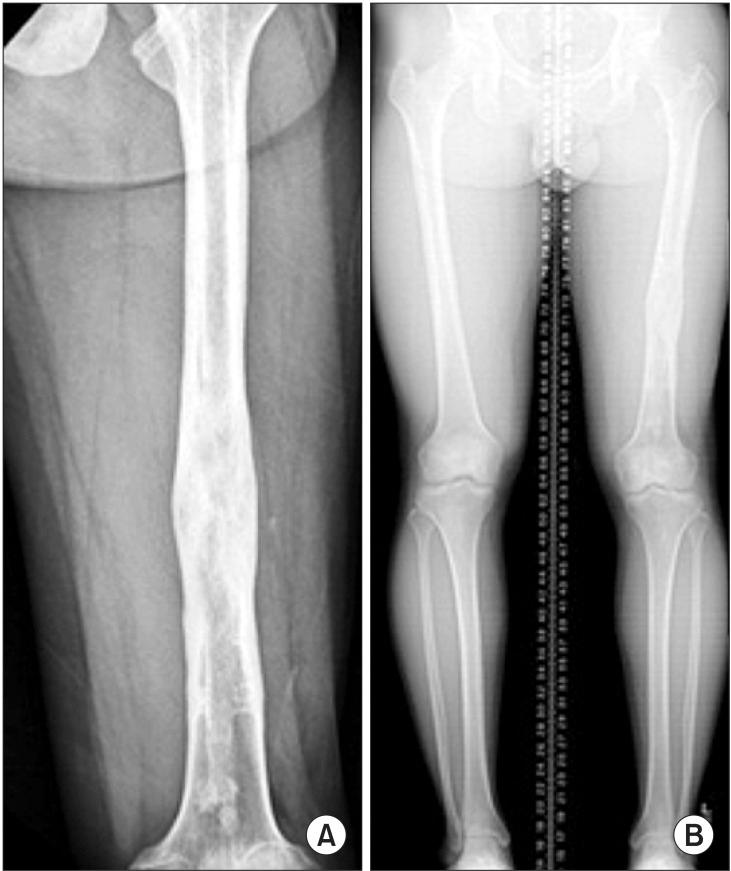

Diaphyseal unicameral bone cysts of the long bone are generally known to originate near the growth plate and migrate from the metaphysis to the diaphysis during skeletal growth. In the case of unicameral bone cysts of diaphyseal origin, recurrence at the same location is extremely rare. We report a case of recurrence of a unicameral bone cyst in the diaphysis of the femur that developed 8 years after treatment with curettage and bone grafting. We performed bone grafting and lengthening of the affected femur with an application of the Ilizarov apparatus over an intramedullary nail to treat the cystic lesion and limb length discrepancy simultaneously.

长骨骨干单房性骨囊肿通常起源于生长板附近,并在骨骼生长过程中从干骺端向骨干迁移。对于骨干起源的单房性骨囊肿,在同一部位复发极为罕见。我们报告一例股骨骨干单房性骨囊肿在刮除植骨治疗8年后复发的病例。我们应用Ilizarov装置在髓内钉上对患侧股骨进行植骨和延长,以同时治疗囊性病变和肢体长度差异。